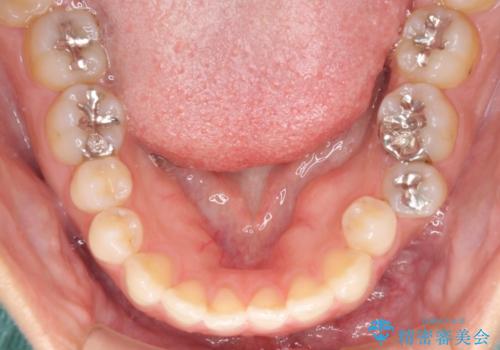

開咬と変色した前歯 インビザライン矯正とオールセラミッククラウン治療

- 前歯の開咬と失活により変色した前歯を気にして来院された患者様です。

開咬の治療は、前歯を閉じるように引っ張り出すよりも、上下臼歯を圧下(骨内にめり込ませる)させることで進める方が長期的に安定した歯列を維持できます。

インビザラインは臼歯の圧下を効果的に行えるため、インビザラインを用いて矯正治療を行うこととしました。

矯正治療が概ね終了した時点で前歯をオールセラミッククラウンにて補綴治療を行い、その後インビザラインにて細かい部分を仕上げていくことしました。